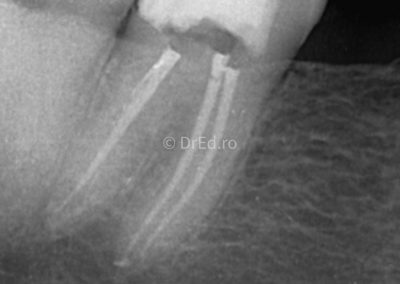

Galerie

Toate imaginile, fotografiile și radiografiile publicate pe acest site sunt protejate prin drepturi de autor și constituie proprietatea exclusivă a Dred.ro.

Aceste materiale sunt furnizate exclusiv în scop informativ și educațional și nu conțin date cu caracter personal sau informații care permit identificarea pacienților, în concordanță cu legislația privind protecția datelor cu caracter personal și GDPR.

Reproducerea, copierea, distribuirea, publicarea, transmiterea, modificarea sau orice altă utilizare, integrală ori parțială, a acestor materiale, în orice formă și prin orice mijloace, fără consimțământul prealabil scris al titularului drepturilor, este strict interzisă și poate atrage răspunderea civilă și/sau penală, în condițiile legii aplicabile privind drepturile de autor și protecția proprietății intelectuale.